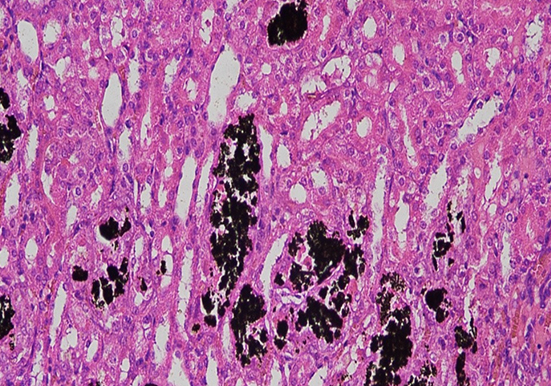

染色原理:利用银离子与组织中的磷酸钙盐或碳酸钙盐发生反应,在酸性条件下,钙盐中的钙离子被银离子取代,形成磷酸银或碳酸银沉淀。这些银盐沉淀在光照条件下,会发生光化学降解反应,被还原为黑色的金属银颗粒,从而使钙盐沉积部位在显微镜下呈现黑色或棕黑色,与周围未钙化的组织形成鲜明对比。

染色处理:把切片浸泡在含 5% 硝酸银的溶液中,暴露于光源下,时间通常为 15-60 分钟,具体取决于钙化程度和组织类型。